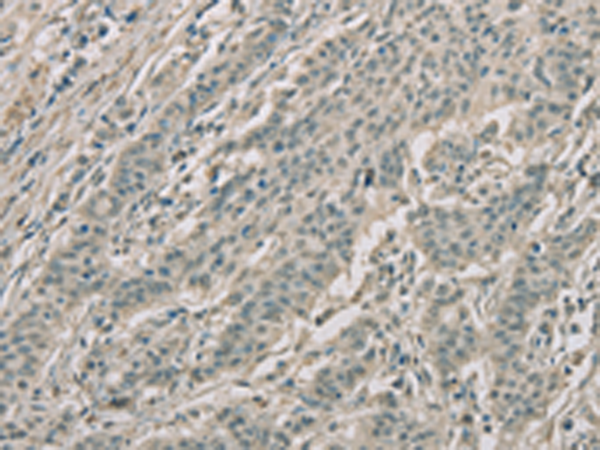

分类: 科研抗体货号: P08265别名: DEL1应用: WB,IHC反应种属: Human, Mouse